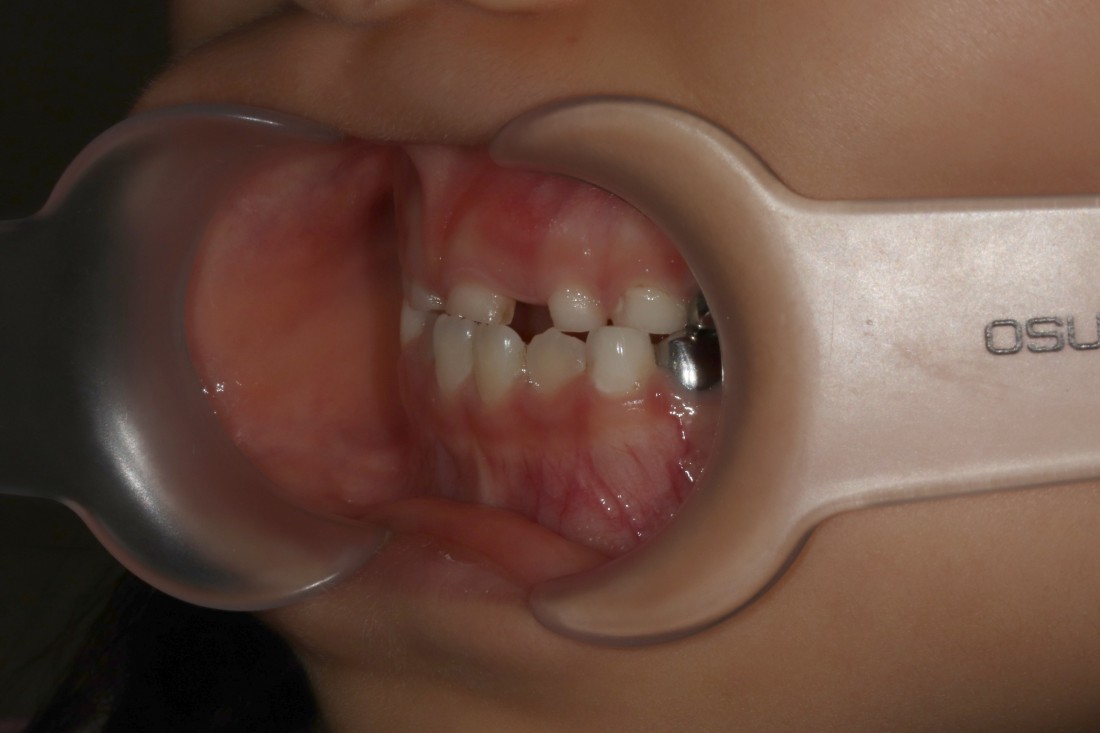

반대교합이란?

윗니와 아랫니가

반대로 맞물리는 교합.

윗니가 아랫니를 덮지 못하고

그 반대로 맞물리며,

소아부정교합 중에서

반대교합의 경우에는

정상교합에 비하여

아랫니, 아래턱이 많이 튀어나와 있어

부모님들께서도 조기에 발견하실 수 있는데요.